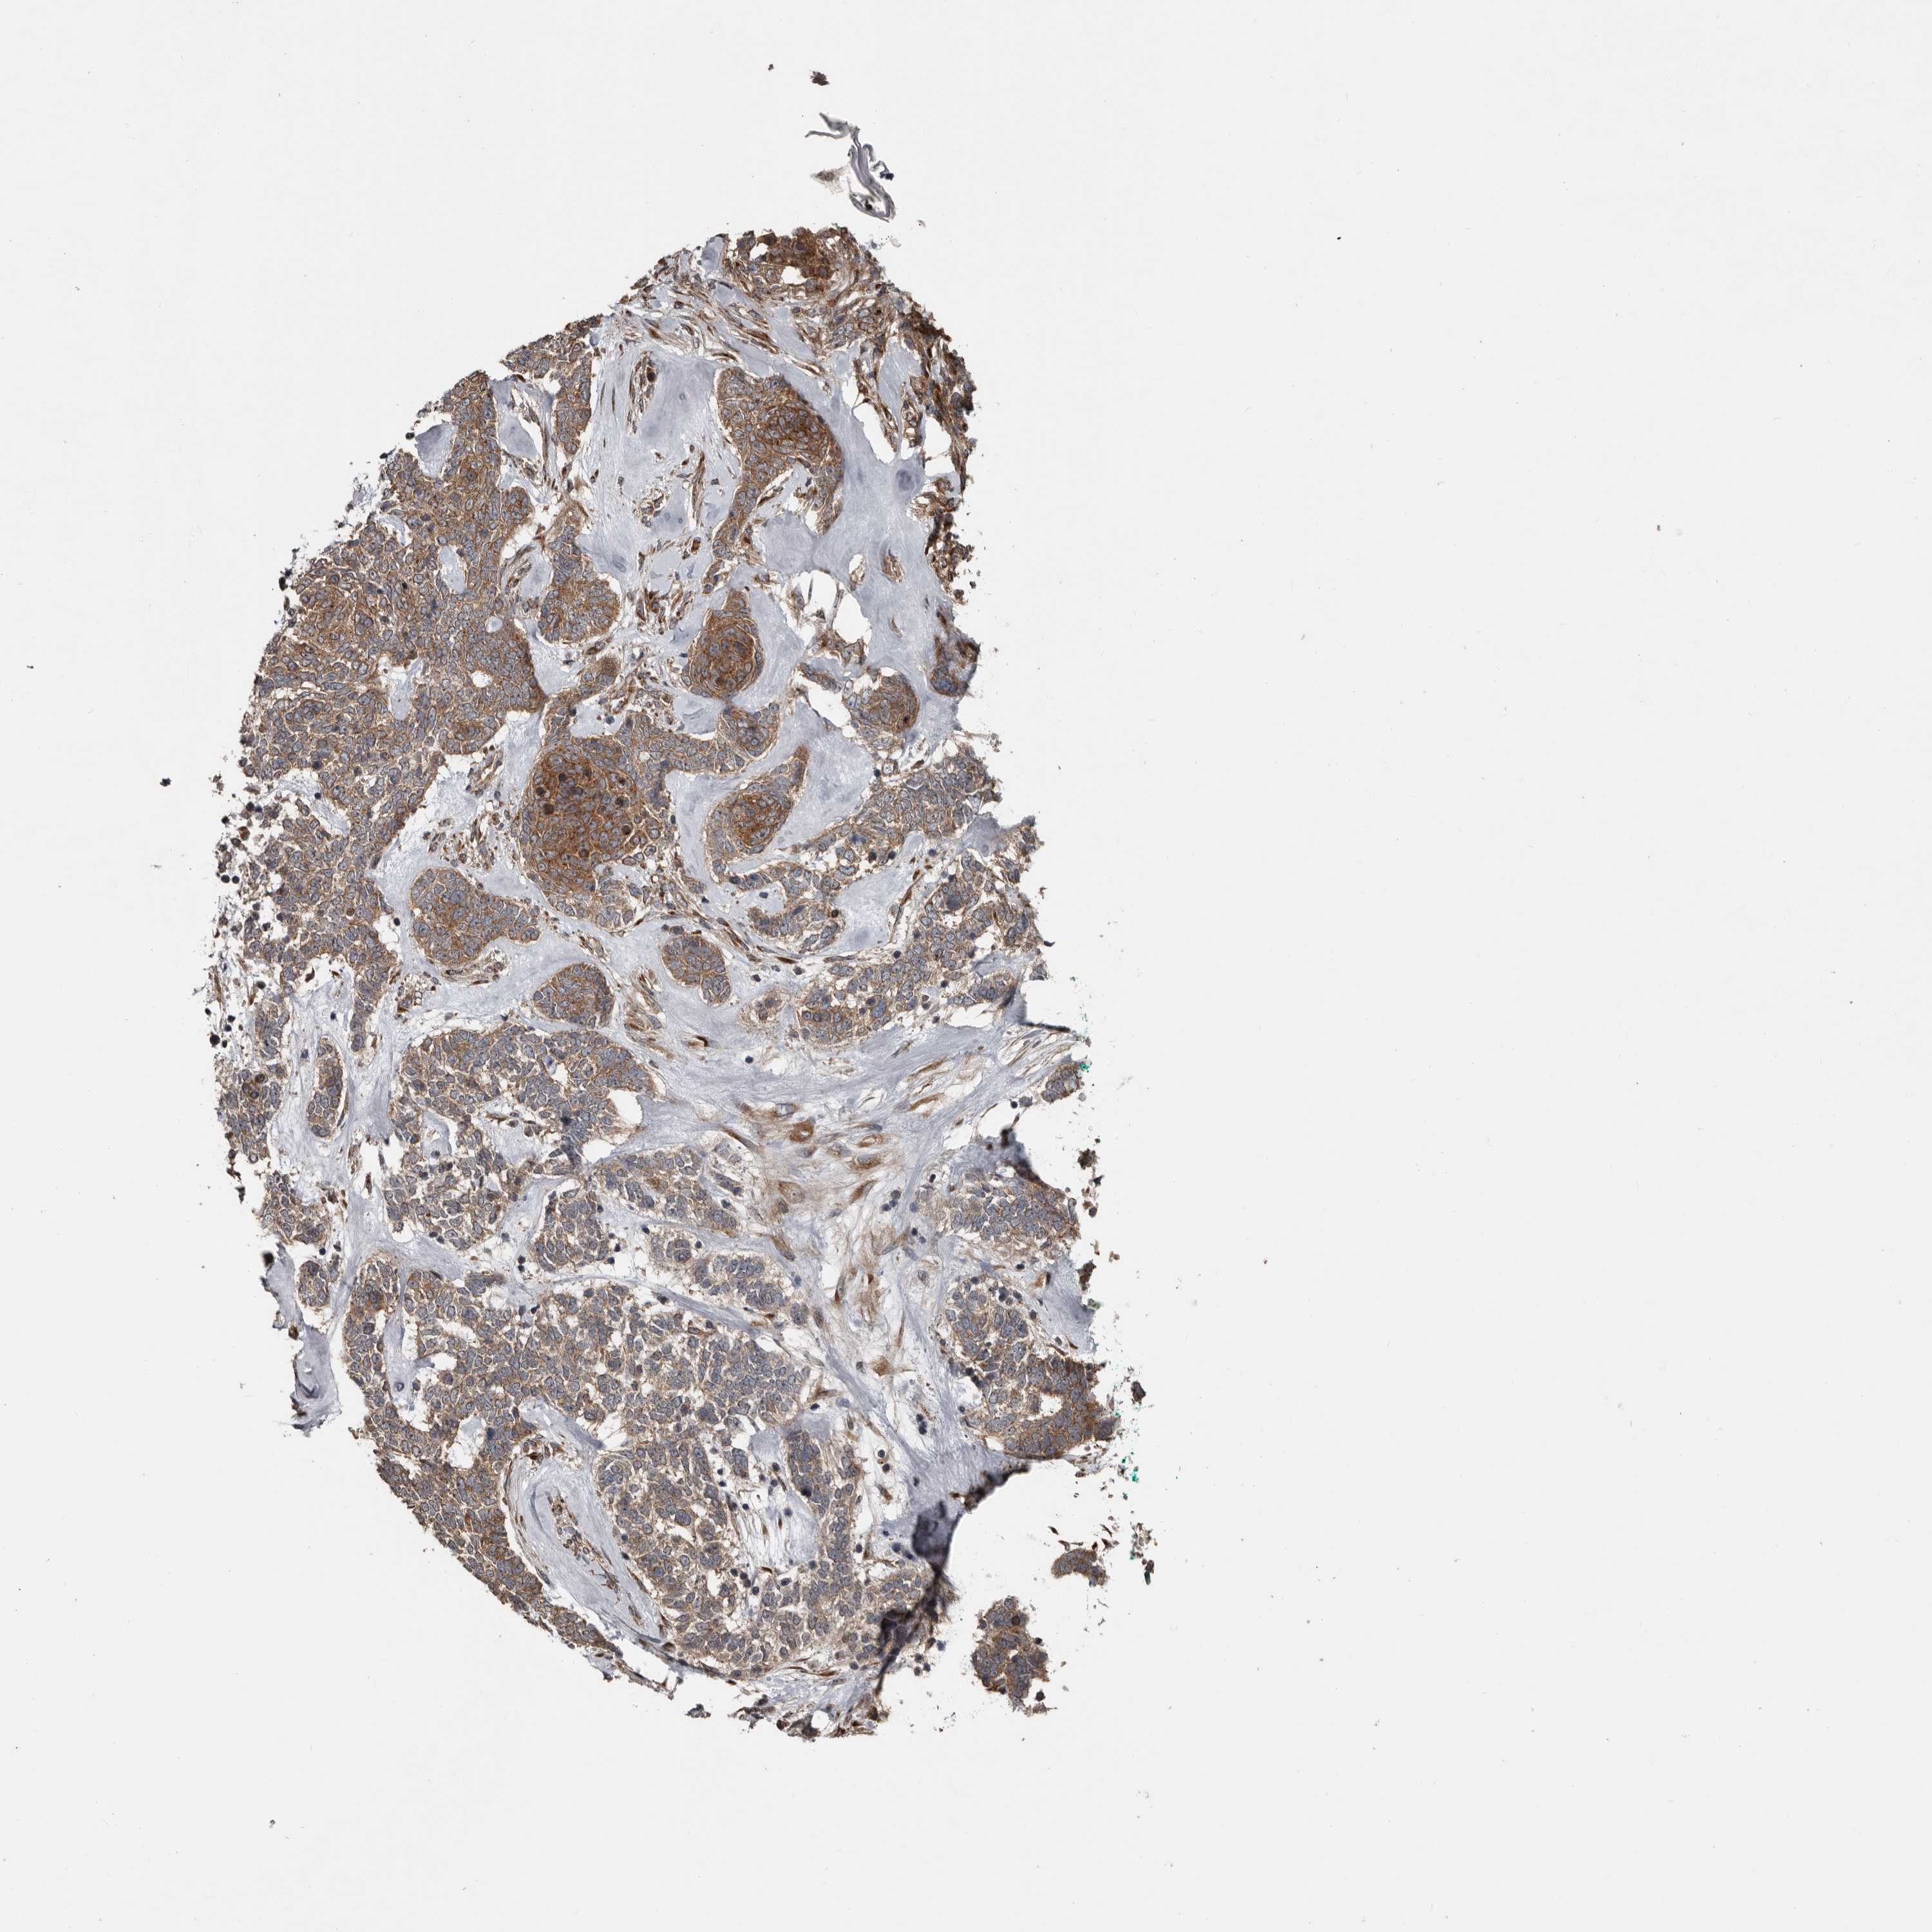

SKIN CANCER - Protein expressioni

A mouse-over function shows sample information and annotation data. Click on an image to view it in a full screen mode. Samples can be filtered based on level of antibody staining by selecting one or several of the following categories: high, medium, low and not detected. The assay and annotation is described here.

Each image is clickable and will lead to virtual microscopy that enables deeper exploration of all samples and also displays staining intensity scores, fraction scores and subcellular localization as well as patient and tissue information for each sample.

Antibody HPA028584

Squamous cell carcinoma, NOS

Squamous cell carcinoma, metastatic, NOS